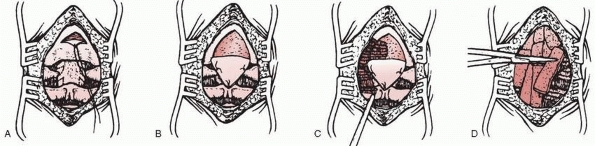

children in whom the posterior elements are absent at C1 or separation

osteogenic tissue layer for the bone graft (Fig. 18-24).125

![]() |

FIGURE 18-24 Technique of occipitocervical arthrodesis used when the posterior arch of C1 is absent. A. Exposure of the occiput, atlas, and axis. B. Reflection of periosteal flap to cover defect in atlas. C. Decortication of exposed vertebral elements. D.

Placement of autogenous cancellous iliac bone grafts. (From Koop SE, Winter RB, Lonstein JE. The surgical treatment of instability of the upper part of the cervical spine in children and adolescents. J Bone Joint Surg Am 1984;66:403, with permission.) |

to about C3, with care not to expose below C2 to avoid extension of the

carried proximally. Extraperiosteal dissection is used to approach the

triangular incision directly on the posterior skull, with the apex

processes of C2 (see Fig. 18-24B). The apex of

(see Fig. 18-24C).